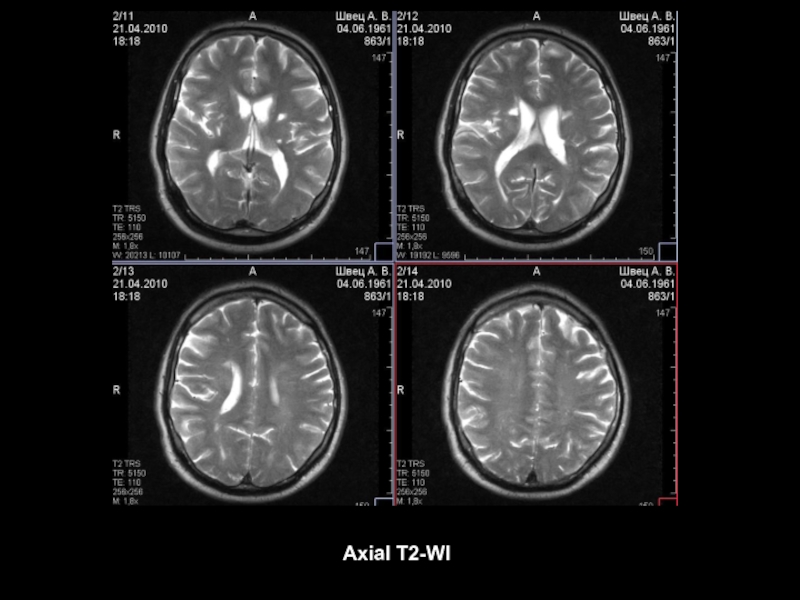

Axial T2-WI